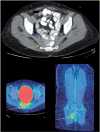

The purpose of this article is to familiarize the reader with the anatomy of the major pelvic nerves and the clinical features of associated lumbosacral plexopathies. To demonstrate this we illustrate several cases of malignant lumbosacral plexopathy on computed tomography, magnetic resonance imaging, and positron emission tomography/computed tomography. A new lumbosacral plexopathy in a patient with a prior history of abdominal or pelvic malignancy is usually of malignant etiology. Biopsies may be required to definitively differentiate tumour from posttreatment fibrosis, and in cases of inconclusive sampling or where biopsies are not possible, follow-up imaging may be necessary. In view of the complexity of clinical findings often confounded by a history of prior surgery and/or radiotherapy, a multidisciplinary approach between oncologists, neurologists, and radiologists is often required for what can be a diagnostic challenge.